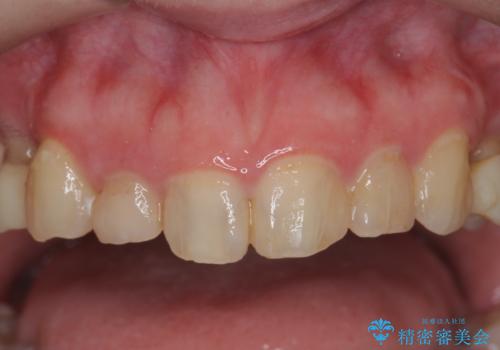

多発した前歯の重度虫歯治療

- 放置した虫歯の歯がボロボロになってしまい治療を希望され来院されました。

残根状態の歯、神経まで虫歯が達し失活した歯、歯肉縁下まで及んだ虫歯が多数認められます。

まず虫歯を拡大鏡、マイクロスコープ下で丁寧に取り除き歯肉縁下の虫歯を歯周外科により解決したのち、ジルコニアクラウン製作を行っていきます。

丁寧な虫歯の除去・歯周組織の整備、適合の良い精密なセラミッククラウンの製作といった丁寧な治療の積み重ねが良好な治療結果を得ることにつながります。